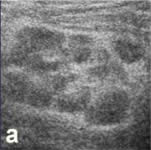

| а - продольное сканирование, исследование в В-режиме.

В просвете отростка определяются 2 каловых камня (эхо-плотные

включения с акустической тенью). |